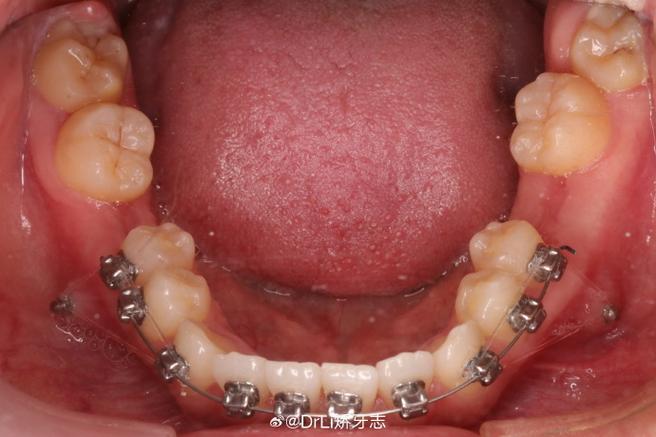

(图片来源网络,侵删)- 推簧施加的力量如果过大,或者力量没有精确地沿着牙齿移动的轴心方向施加,就容易导致牙齿发生倾斜、旋转或整体位置偏移,而不是单纯地按预期方向移动。

- 医生在放置推簧时,可能没有精确地定位在牙齿的“中心”,或者弹簧本身发生了变形、移位。

如果牙齿上粘接的托槽或颊管(用于固定推簧的装置)在放置推簧时发生了松动、脱落或者位置不精确,也会导致推簧施加的力量方向错误,从而影响牙齿移动。

- 检查推簧的位置、形态、是否在位。

- 评估门牙的移动方向、倾斜角度、是否有旋转、松动度。

- 检查相关牙齿的托槽/颊管是否牢固、位置是否正确。